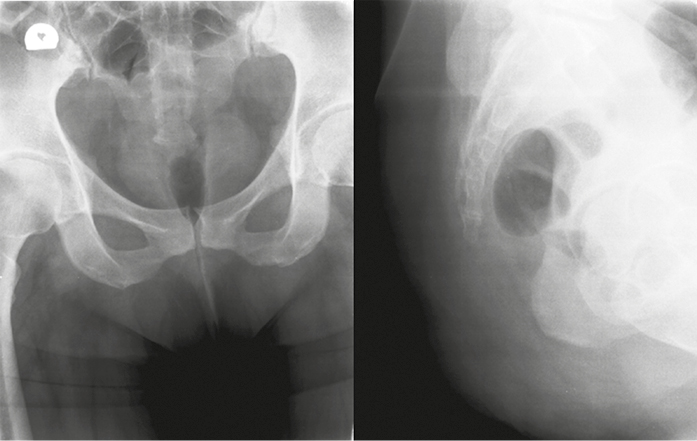

Первое клиническое наблюдение. Пациентка М., 40 лет, находилась на лечении в клинике военной травматологии и ортопедии Военно-медицинской академии им. С.М. Кирова в феврале 2016 г. Анамнез: в октябре 2015 г. получила травму копчика при падении на ягодицы; находилась на стационарном лечении в травматологическом отделении многопрофильной больницы по поводу закрытого оскольчатого перелома копчика, получала консервативную терапию; далее в течение 7 месяцев получала амбулаторное лечение по месту жительства (обезболивающие препараты, физиотерапевтическое лечение) без эффекта. В клинике у больной был выявлен несросшийся неосложненный оскольчатый перелом пятого крестцового (S5) позвонка, первого копчикового сегмента (Co1) с подвывихом копчика и болевым синдромом (рис. 1, 2). Индекс ВАШ — 8 баллов. В связи с длительно сохраняющимся болевым синдромом и неэффективностью консервативного лечения выполнена операция: резекция S5 позвонка, удаление копчика (рис. 3). Послеоперационное течение без осложнений. Пациентка выписана на 5-е сутки после операции. Значения индекса ВАШ составили через 1 месяц 2 балла, в дальнейшем — 1 балл. По шкале удовлетворенности операцией — «полностью удовлетворена».

Рис. 1. Рентгенография крестца и копчика пациентки М. до операции

Fig. 1. X-ray of the sacrum and coccyx of patient M. before surgery

Рис. 2. Компьютерная томография крестца и копчика пациентки М. до операции

Fig. 2. CT of the sacrum and coccyx of patient M. before surgery